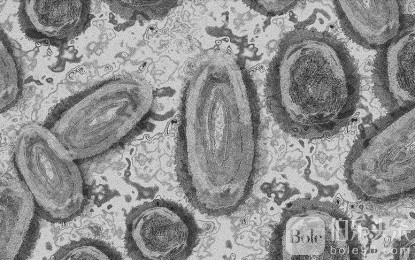

目前在刚果民主共和国和非洲大陆其他地区传播的 mpox 变种被认为比导致 2022 年开始的全球疫情的“进化枝 2”变种更具传染性和致命性。